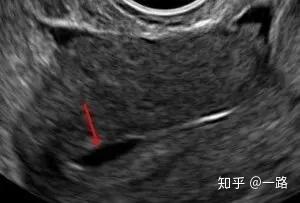

經大量研究發現,子宮內膜超聲形態(包括子宮內膜厚度、回聲、血流等)是判斷胚胎移植的種植窗口期的一個重要的評估指標。超聲波顯示正常子宮內膜種植窗時期厚度一般約在7-10mm之間,容積不應該小于2ml且內膜能量多普勒面積多在5㎜以上。